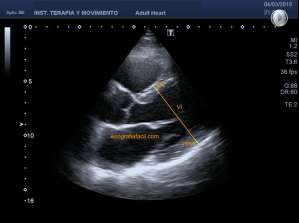

142. Ecocardiografía.Plano Apical 4 cámaras